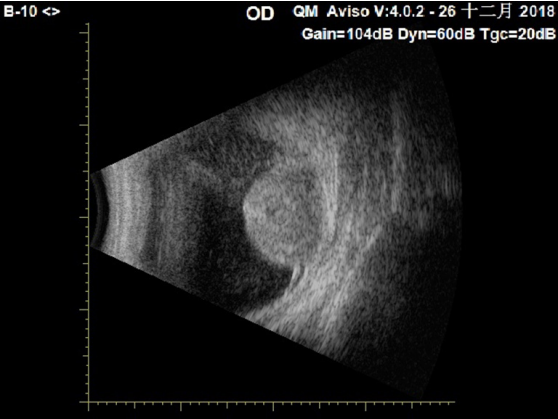

3例眼球摘除标本经固定后均根据术前检查显示的肿瘤部位,行肿瘤最大面切开眼球,肿瘤切面呈黄白色,镜下见肿瘤均位于脉络膜内,伴表面视网膜脱离,网膜下渗出(图3A),肿瘤内血管丰富,呈裂隙状,肿瘤细胞细胞质透亮,多呈实性片巢状排列,部分呈腺管、腺泡状排列,大部分细胞细胞质透明,部分细胞细胞质呈嗜伊红颗粒状(图3B),核小,形状不一,核仁不明显,部分核空泡状,可见核分裂象(图3C),部分区可见肿瘤细胞坏死(图3D)。肿瘤细胞细胞质PAS染色(+),不耐淀粉酶消化(图3E)。免疫组织化学染色显示肿瘤细胞CK、VIM、CK8、CD10、PAX8阳性(图3F~3H),CK7、CK19、CK20、CEA、TTF-1、S-100、CD56、SYN、HMB45、DES、MSA、SMA、LCA、CD68均为阴性,增殖活性ki-67指数在5%~40%。例1和例3结合形态及免疫组织化学,考虑为转移性CC-RCC,建议在肾脏等处寻找原发灶。例2结合形态、免疫组织化学及病史,符合脉络膜转移性CC-RCC(表1)。

图3 光镜下观察例3脉络膜转移性CC-RCC患者肿瘤组织

Figure 3 Choroidal metastatic CC-RCC of Case 3

(A)例3肿瘤起源于脉络膜,伴表面视网膜脱离,网膜下渗出(HE,×40);(B)例3患者大部分肿瘤细胞细胞质透明,部分细胞质呈嗜伊红颗粒状,呈实性片巢状及腺管状排列(HE,×200);(C)例3患者大部分肿瘤细胞核小,核仁不明显,部分核空泡状,可见核分裂象(箭头;HE,×400);(D)例3患者肿瘤组织内部分区可见肿瘤细胞坏死,右侧为坏死肿瘤细胞(箭头;HE,×400);(E)例3患者肿瘤细胞细胞质PAS染色(+),不耐淀粉酶消化(PAS,×400);(F)例3患者肿瘤细胞表达VIM(免疫组织化学,×400);(G)例3患者肿瘤细胞表达CD10(免疫组织化学,×400);(H)例3患者肿瘤细胞表达PAX8,表达于细胞核上(免疫组织化学,×200)。

(A) Tumor derived from the choroid with retinal detachment and subretinal exudation (HE, ×40); (B) Tumor cells contained clear or granular cytoplasm arranged in solid and glandular patterns (HE, ×200); (C) Most tumor cells showed small nuclei with inconspicuous nucleoli, some tumor cells showed vesicular nuclei and mitotic figure (arrow; HE, ×400); (D) Viable tumor was juxtaposed to necrotic tumor (arrow; HE, ×400); (E) Tumor cells contained PAS-positive granules which could be abolished by diastase pretreatment (PAS,×400); (F) Tumor cells showed VIM positive (IHC, ×400); (G) Tumor cells showed CD10 positive (IHC, ×400); (H) Tumor cells showed PAX8 positive with nuclear expression (IHC, ×200).